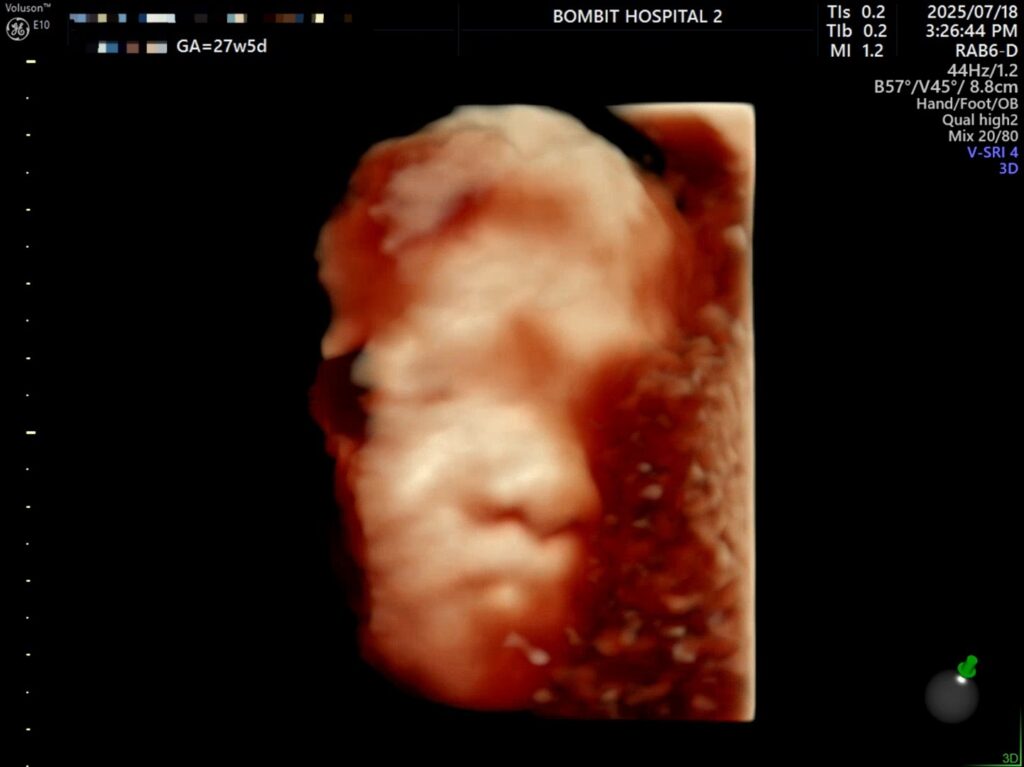

7월 18일, 27주 5일.

어제 단비의 입체초음파를 보았다.

입체초음파로 본 단비는 처음에 완전히 엎드려있었다. 바닥을 향해 엎드려서 얼굴을 파묻고 귀 밖에 안 보여줌.. ㅜㅜ

그렇게 다행스럽게도 단비 얼굴을 볼 수 있게 되었다.

– 처음에 보여준 귀.. 귀욥